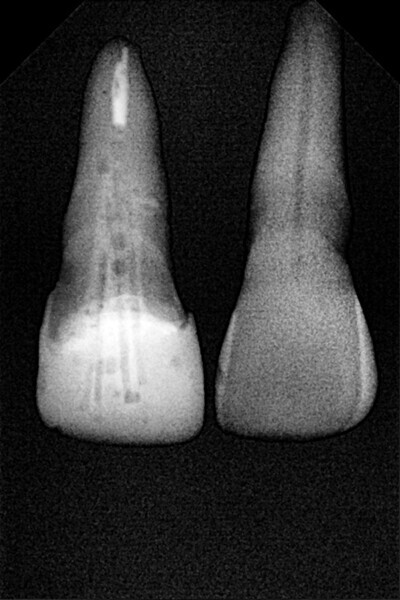

1. functional and aesthetic reconstruction of a maxillary anterior tooth using fibre-reinforced flexible micro-posts after endodontic treatment (Figs. 3–20);

Example 1—showing functional and aesthetic reconstruction of a maxillary anterior tooth using fibre-reinforced flexible micro-posts after endodontic treatment.